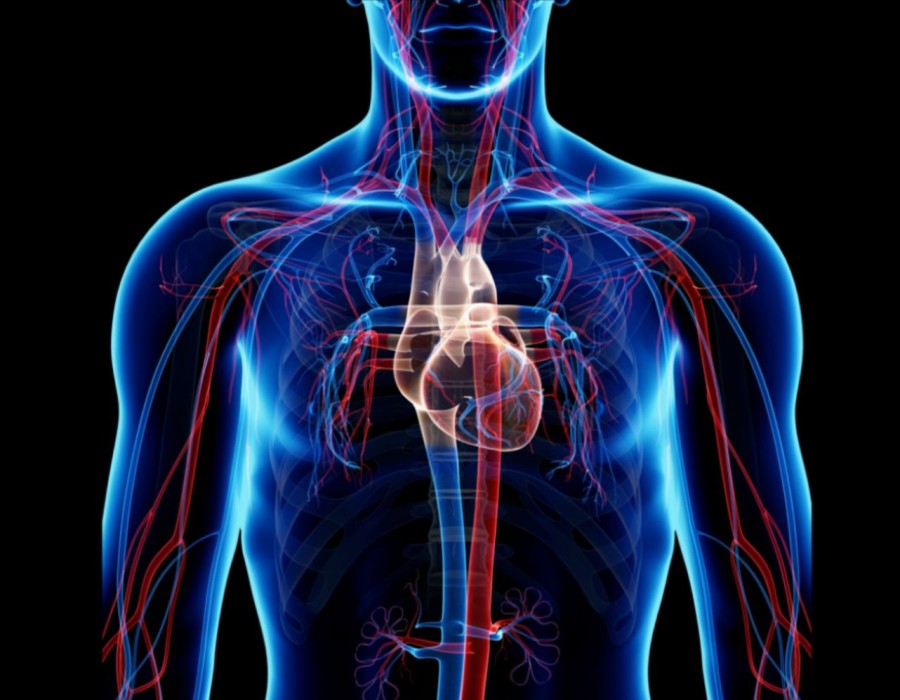

The Cardiovascular Devices Market encompasses a wide range of products, including pacemakers, stents, heart valves, defibrillators, monitoring devices, and more. These devices are essential in managing cardiovascular diseases (CVDs), which remain the leading cause of mortality globally.

Cardiovascular devices are medical equipment used to diagnose, monitor, and treat heart and blood vessel problems. Important examples include the replacement or repair of heart valves, the use of stents to keep arteries open, pacemakers to regulate heart rhythms, and catheters for medical or diagnostic uses like angioplasty. Heart monitors to continually monitor heart activity, implanted cardioverter defibrillators (ICDs) to treat severe arrhythmias, heart pumps such as LVADs to assist the heart pump blood, and electrocardiogram (ECG) equipment to record heart activity are examples of further devices. When it comes to the management and treatment of cardiovascular disorders, these gadgets significantly enhance patients' overall health and quality of life.